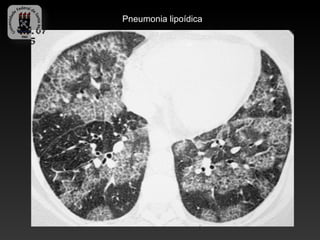

Pneumonia lipoídica